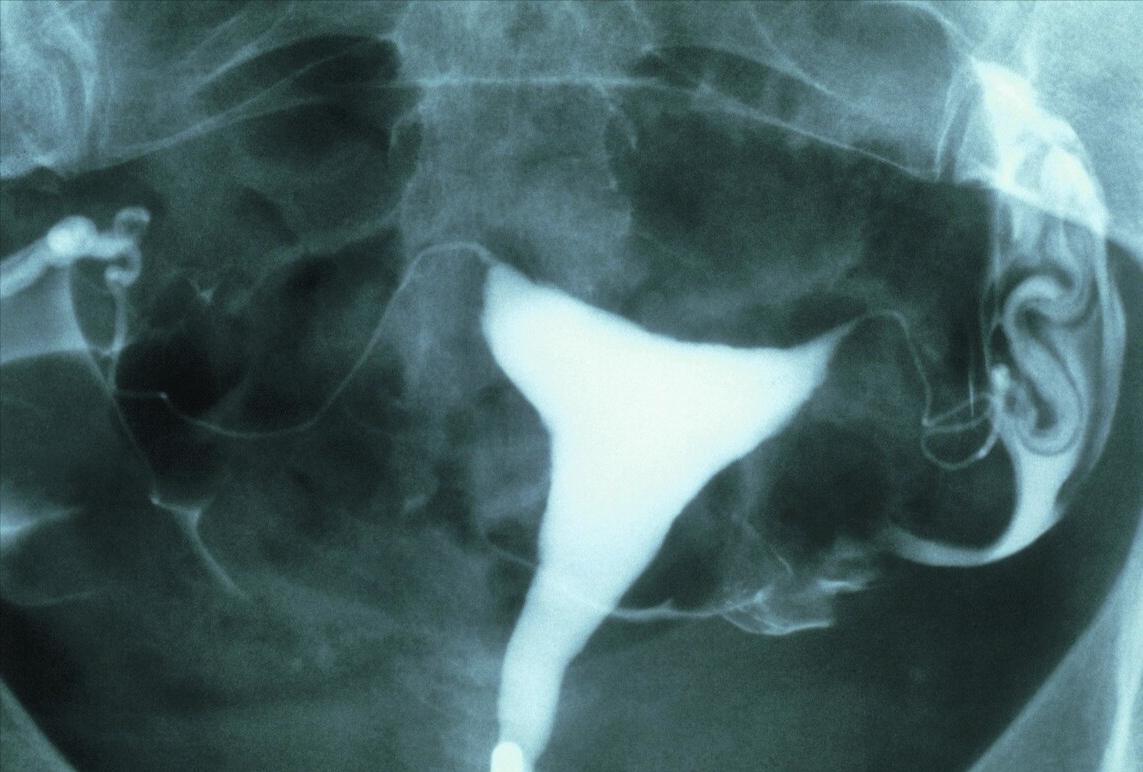

子宫颈物理治疗对于治疗的指征把握要求非常严格,应由有经验的阴道镜医生进行充分阴道镜评估,并进行子宫颈取样活检病理诊断后,如能满足治疗的指征,方可采用子宫颈物理治疗。